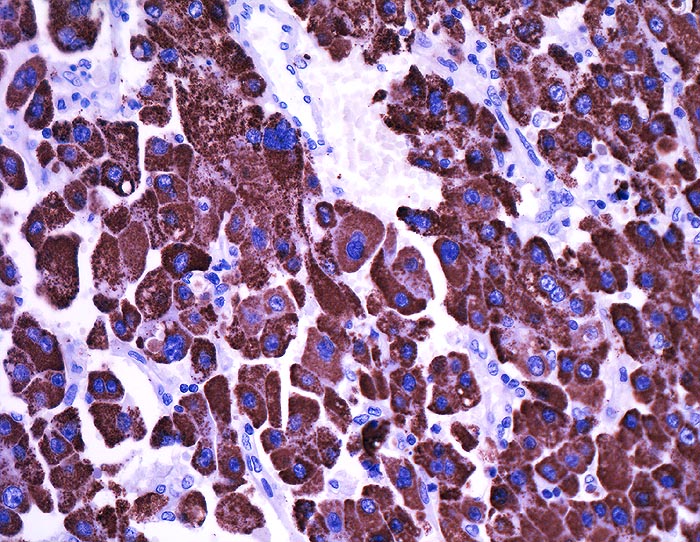

Hep Par 1 (Hepatocyte Paraffin 1)

- Anfärbung:

- Zytoplasma grob granulär ohne canaliculäre Akzentuierung.